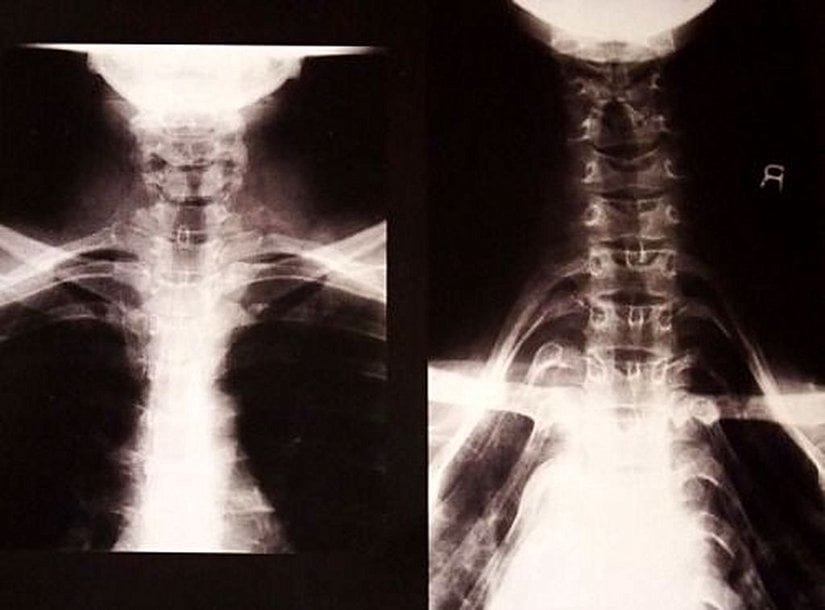

Boynu uzattığına inanılan bu işlem, aslında boynu uzatmıyor; yani boynun daha uzun görünmesi sadece bir illüzyondan ibaret! Boyna takılan yaklaşık 10 kiloluk bu halkalar (tek bir halka 10 kilogram ağırlığa erişebiliyor!), köprücük kemiğini aşağı iterek göğüs kafesi üzerinde bir baskı yaratıyor ve bu sayede, boyun sanki uzamış gibi gözüküyor. Ancak X-ışını görüntüleri, gerçek bu uzamanın yaşanmadığını görmek için yeterli: